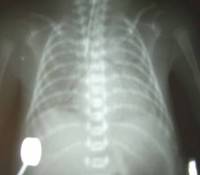

成人呼吸窘迫綜合徵[影像學表現]

1.早期:肺紋理增重模糊,可有小斑片狀陰影,也可無異常X線表現。2.中期:肺內斑片狀或大片狀融合陰影,兩肺外帶比內帶重。3.晚期:兩肺廣泛的片狀陰影,甚至兩肺廣泛實變,心影輪廓消失,僅肋膈角處有少量含氣陰影。此期常合併感染,出現團塊、空洞或膿胸。

4.恢復期;約在發病1周后,病變陰影逐漸消失。5.必須結合病史、臨床表現和血氣分析綜合判斷,氧分壓小於8kPa(60mmHg),一般給氧治療無效,並需除外心源性或非心源性肺水腫。

成人呼吸窘迫綜合徵檢查兩肺有無肺紋理增加、斑片狀陰影或兩肺廣泛密度增加及呈“白肺”外觀。